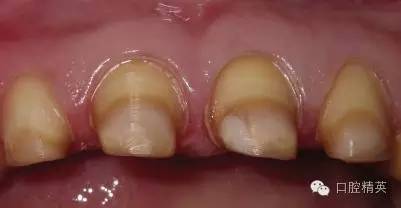

關(guān)于基礎(chǔ)治療。牙周治療和根管治療是美觀修復(fù)的基礎(chǔ)。根據(jù)術(shù)前檢查,常規(guī)先行全口潔治,必要時(shí)局部深層次的牙周治療,待牙周情況穩(wěn)定后,再考慮牙體預(yù)備與取模(見圖1、2)。在牙周炎未控制或牙齦紅腫的情況下,是不可能預(yù)備好牙齒,不可能取得清晰的印模,更談不上成功的美觀修復(fù)。

根管治療更是牙體修復(fù)的基礎(chǔ),根據(jù)術(shù)前診斷,對需要做根管治療的或有必要重新做根管治療的,一定要做到恰充,消除隱患,避免將來冠修復(fù)好后,出現(xiàn)根尖炎癥的問題(見圖3、4、5)。在基礎(chǔ)工作做好后,接下來開始牙體預(yù)備,根據(jù)跟個(gè)人習(xí)慣,選擇合適的車針(圖6、7)。

牙體預(yù)備中支點(diǎn)一定要穩(wěn),手法輕柔,切忌傷及牙齦及鄰牙。由于LAVA冠有著較高的強(qiáng)度,所以牙體預(yù)備較傳統(tǒng)烤瓷冠或其它全瓷冠要少些,最薄可以備0.7mm,最大限度的保留了天然牙體。理想的預(yù)備應(yīng)包括360毅肩臺或水平角不小于5毅的淺凹型肩臺,垂直預(yù)備角度至少有4毅,肩臺預(yù)備內(nèi)側(cè)角和咬合面線角一定要圓滑。當(dāng)然在這一過程中,助手與患者的配合也非常重要,在給醫(yī)生提供一個(gè)清晰舒適的視野的同時(shí),讓患者也要感到舒適,保證牙備的順利進(jìn)行,形成完美的預(yù)備體。牙體預(yù)備示例見圖8。

LAVA 全瓷冠強(qiáng)度高,顏色自然,邊緣高度密合,切端可見半透明感,整體效果理想,與修復(fù)前(見圖1)相比取得了醫(yī)患均滿意的效果。